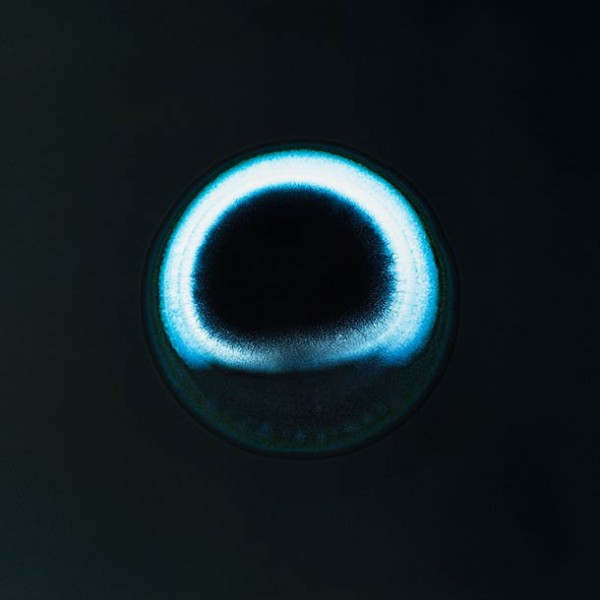

cocaine